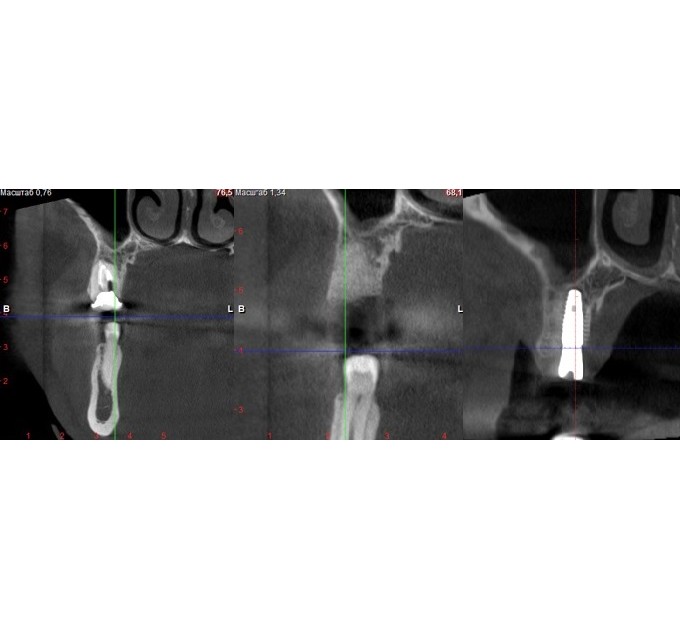

Якщо кістки недостатньо, проводять кісткову пластику і коли кістка збільшиться, виконують імплантацію зубів. Об’єм та щільність щелепної кістки точно визначає стоматолог на підставі комп’ютерної томографії, де вимірюються щелепа, щільність кісток, напрямок коренів, кровоносних судин та м’яких тканин.